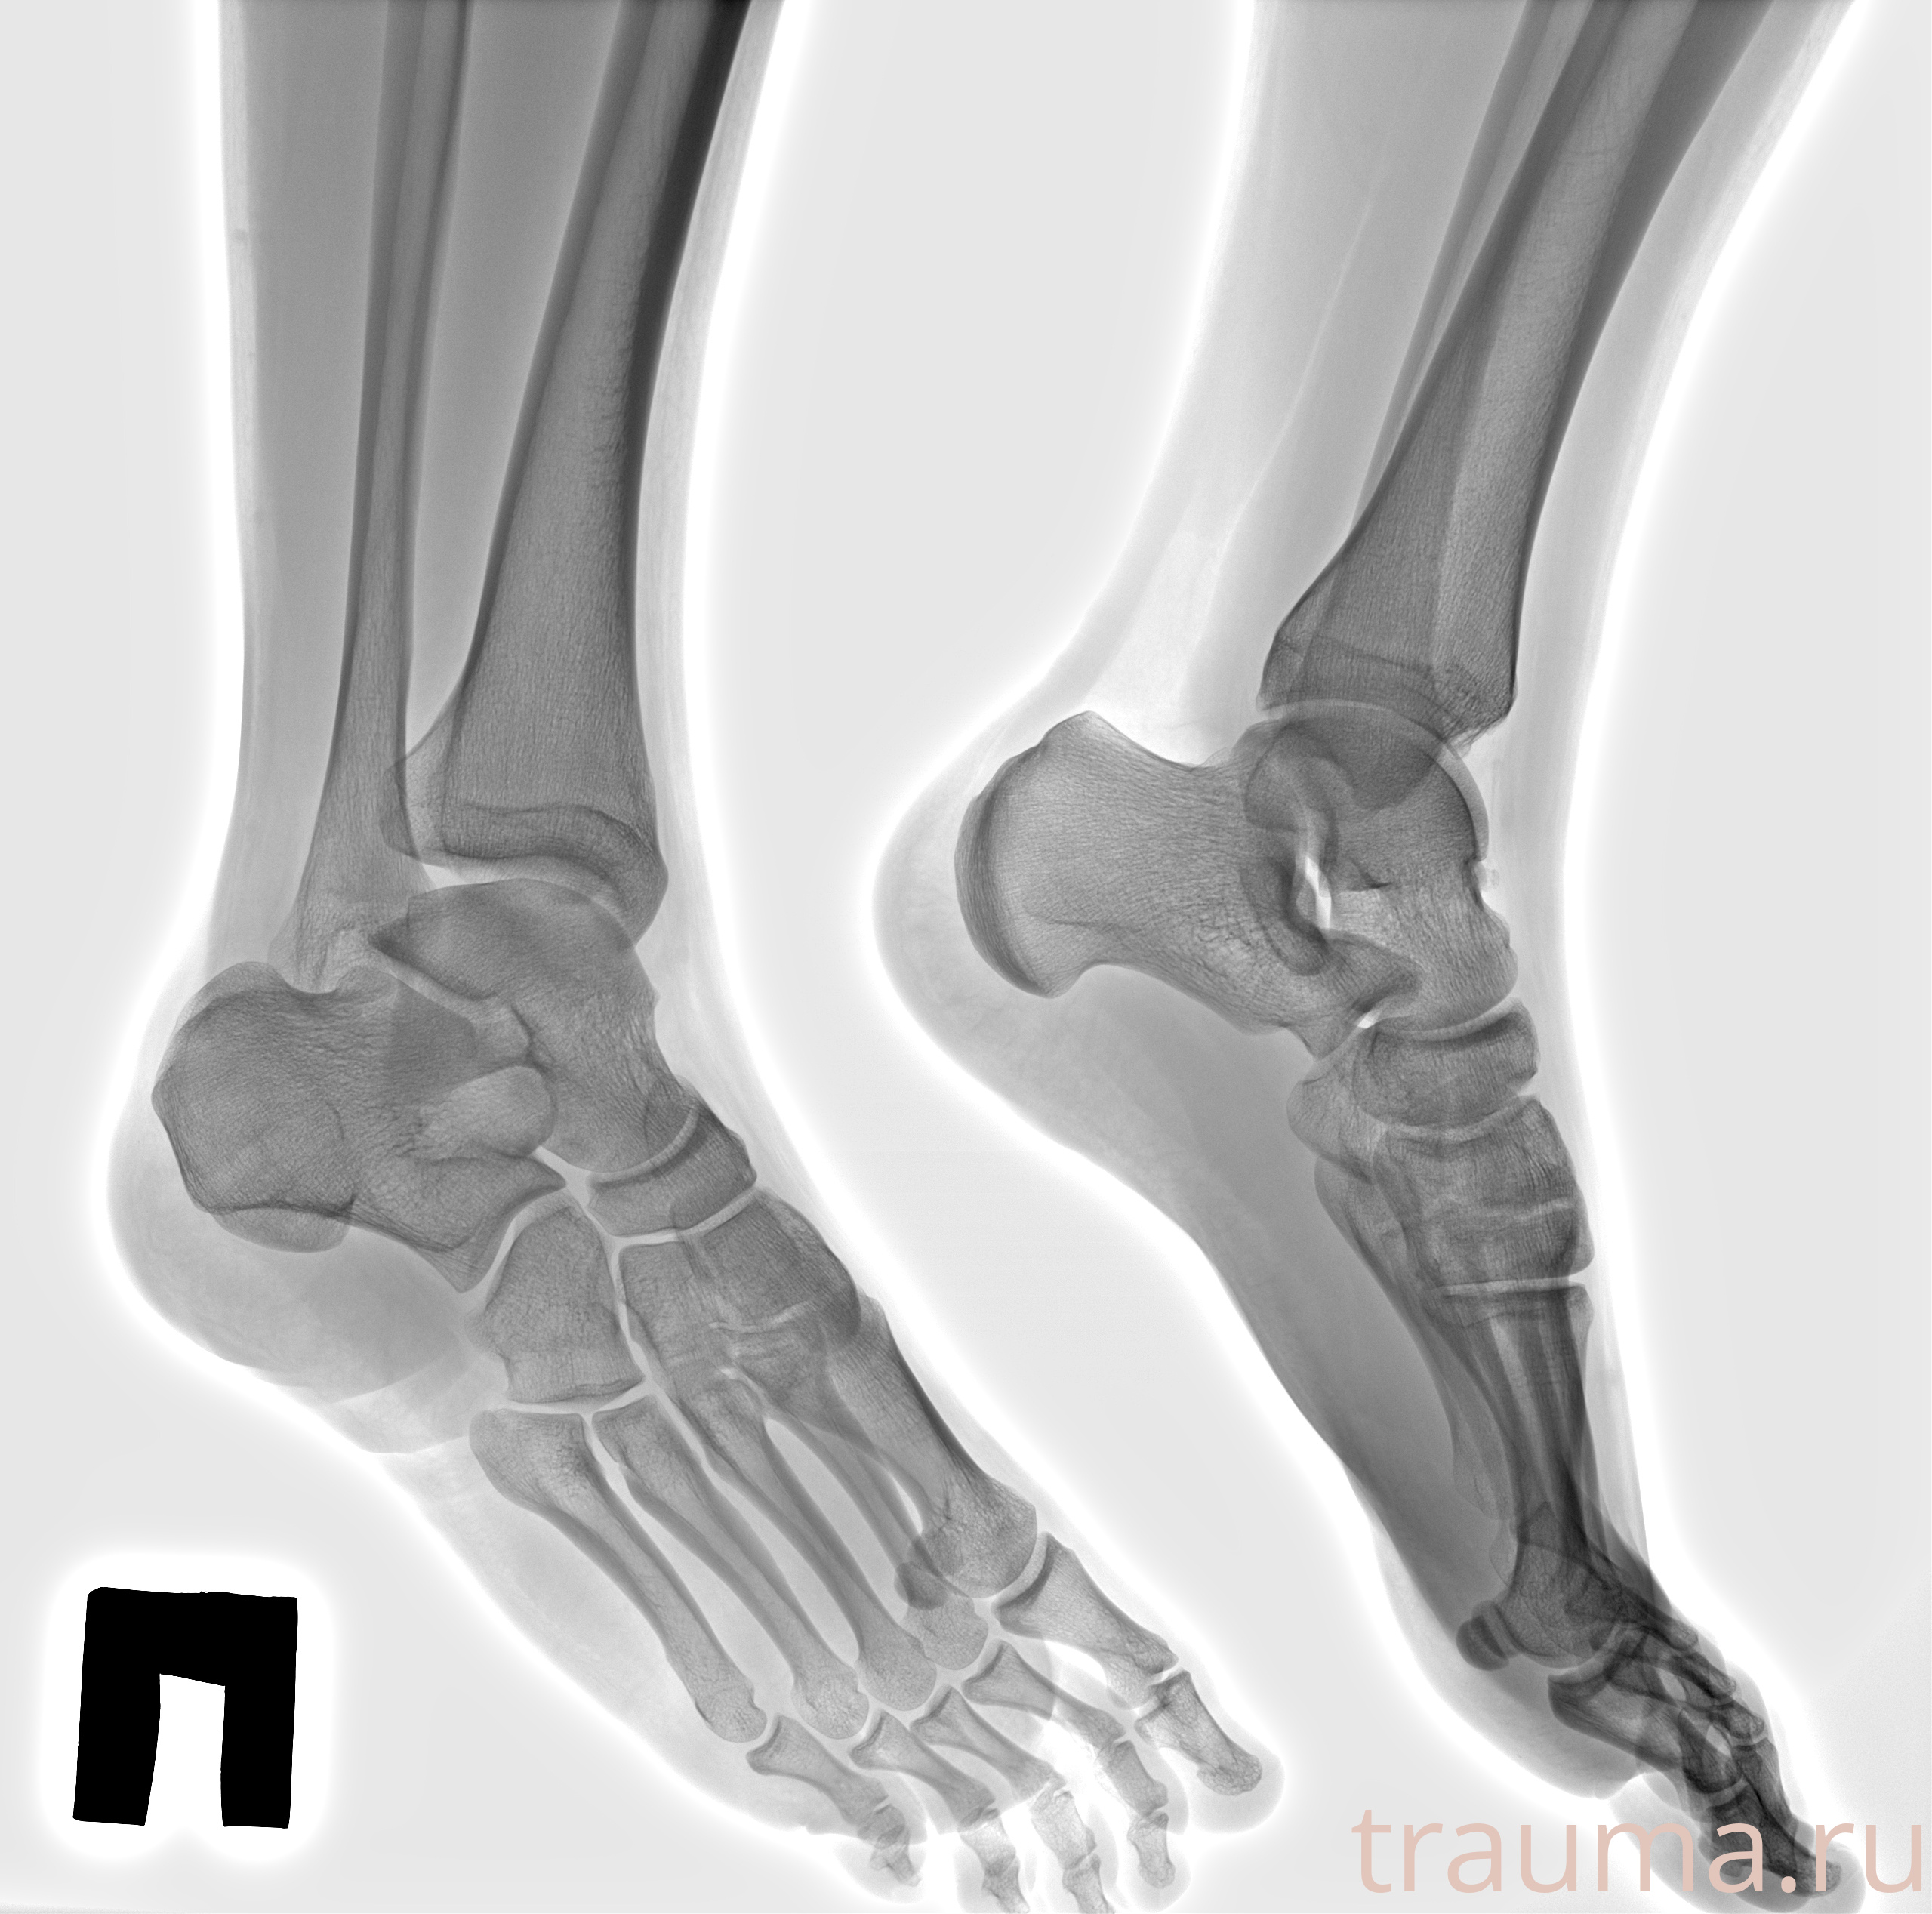

Рентгенограммы

Рентген на дому: по вашему адресу приезжает врач-рентгенолог, травматолог-ортопед с мобильным рентгеновским аппаратом, проводит диагностику травмы или заболевания, делает необходимые рентгенограммы, дает рекомендации по дальнейшему лечению. Получить качественные снимки в домашних условиях возможно благодаря уникальной методике, разработанной МосРентген Центром для института  Склифосовского